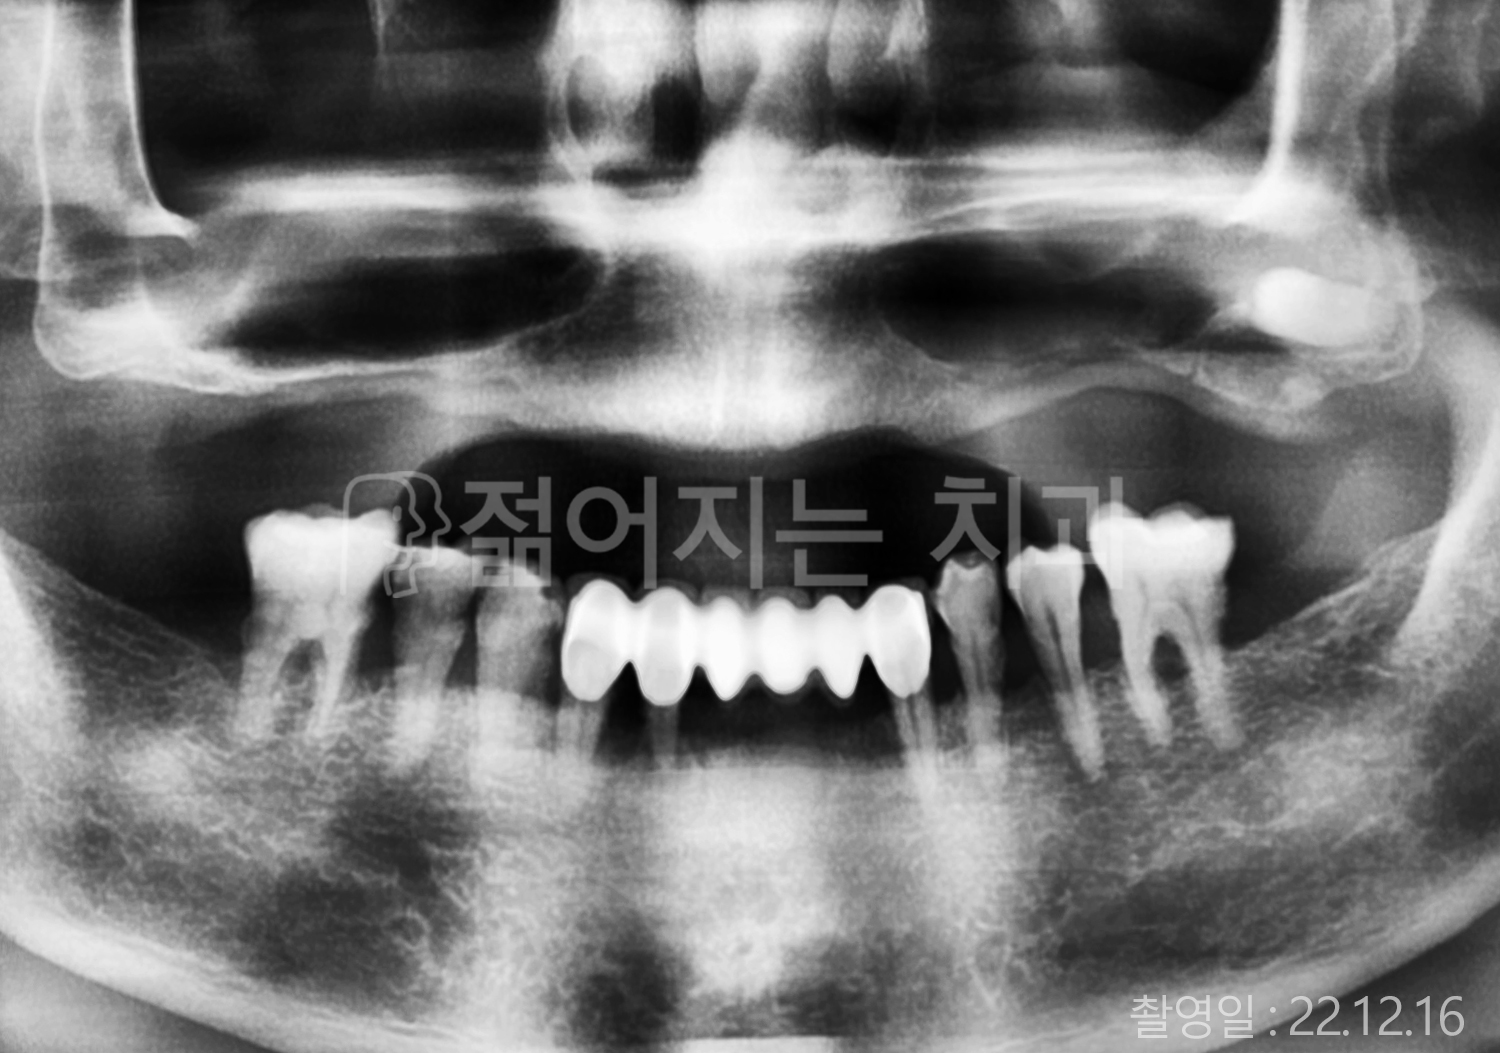

• 40대 전체치아 10개 이상 임플란트

• 50대 전체치아 10개 이상 임플란트

• 50대 고혈압, 당뇨, 고지혈증 전체치아 10개 이상 임플란트